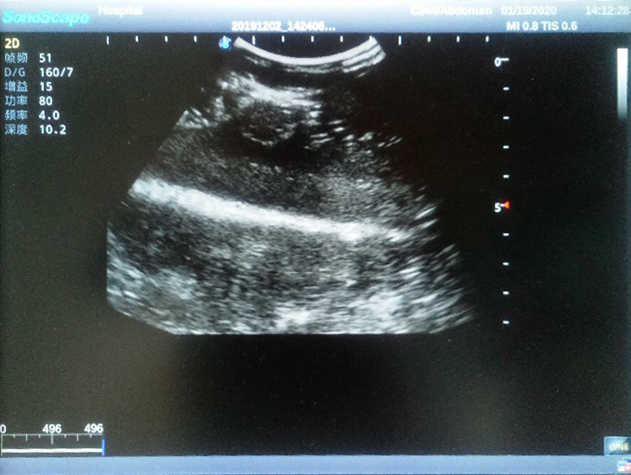

Breast Ultrasound Examination Model

Model TYE1568

The Breast Ultrasound Examination Model allows users to develop and practice the skills necessary to gain proficiency in breast palpation, using ultrasound for normal and abnormal imaging and biopsy. It simulates adult female breasts with realistic size and appearance.

2)  Each model contains 8 space-occupying lesions of varying sizes, different in touch, elasticity and ultrasonogram

4) Biomimetic material allowing users to see clear and real normal tissues and space-occupying lesions that are hyperechoic, hypoechoic and isoechoic as they would see in the clinical environment